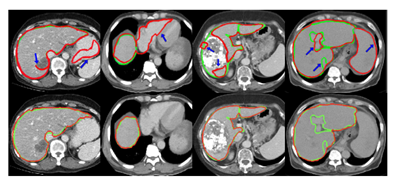

Experiment Result Here is a test on pathological liver segmentation. As shown in Figure 12, the left table 2 shows the DISSM results on top of a CT scan after each stage. As can be seen, each stage progressively improves the result. The visual impact of these improvements can be seen in the first column of the right box-whisker plot. And we can see the performance of different models in this table. DISSM exhibits less variability in DSC and ASSD, which means better robustness and can be seen in the box plot obviously. Since the clinical results are more convincing, they also test on the clinical liver dataset. In Figure 13, as Table 3 highlights, the performance of other models drops off on clinical datasets because the incidence rates, scanners, patient populations, and practices may be unexpected. In comparison, DISSM's performance is much more stable and still achieves very good data. And as shown in Figure 14 it also performs well on Larynx dataset.[2]